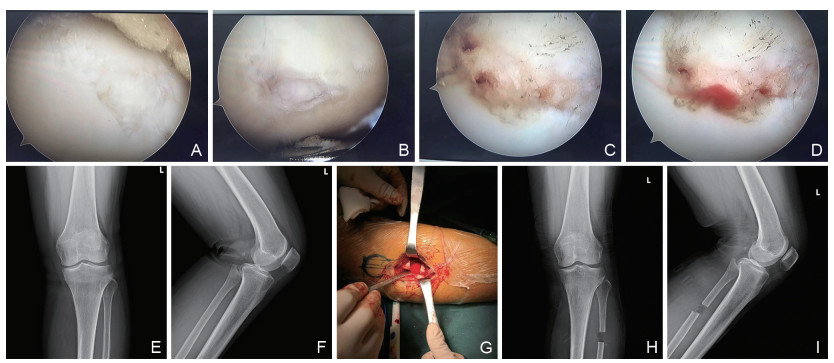

Clinical study of upper fibular osteotomy combined with arthroscopic debridement in the treatment of medial compartment osteoarthritis of knee joint

WANG Xiaocheng, JIA Bo, WANG Yu, WU Yunjian, WANG Qiang

2024, 22(12): 2066-2070. doi: 10.16766/j.cnki.issn.1674-4152.003799

524 4

Abstract:

Objective  The theory of uneven settling of the knee joint provides a new idea for the surgical treatment of knee osteoarthritis (KOA). The objective of this study was to investigate the clinical advantages of superior fibular osteotomy combined with arthroscopic debridement in the treatment of medial compartment osteoarthritis of the knee joint compared to arthroscopic debridement alone.  Methods  The data of 125 patients with medial compartment osteoarthritis of the knee joint who completed treatment in Jinhua Hospital of Traditional Chinese Medicine from January 2021 to June 2023 and were followed up for ≥6 months were collected. According to different treatment methods, they were divided into the control group (72 cases with arthroscopic debridement alone) and the study group (53 cases with superior fibular osteotomy combined with arthroscopic debridement). The changes of femoral tibial angle (FTA), tibial joint space angle, knee range of motion (ROM), hospital for special surgery (HSS) score and synovial fluid interleukin-6 (IL-6) and interleukin-1β (IL-1β) were compared between the two groups, and the incidence of surgery-related complications were analyzed.  Results  Six months after surgery, the levels of FTA [(180.21±1.90)° vs. (182.89±1.75) °], tibial joint space angle [(1.58±0.37)° vs. (3.09±0.61) °] and IL-6 and IL-1β in synovial fluid of knee joint in the study group were lower than those in the control group. The ROM [(91.23±7.05)° vs. (82.86±6.72)°] and HSS scores [(74.50±7.25) points vs. (65.12±6.37) points] were higher than those of the control group (P < 0.05), and the improvement of knee joint function was better than that of the control group (P < 0.05). There was no significant difference in the incidence of complications between the two groups (P>0.05).  Conclusion  Upper fibular osteotomy combined with arthroscopic debridement is an effective treatment for medial compartment osteoarthritis of the knee joint, which can significantly improve the lower limb force line, reduce inflammatory injury of the knee joint and improve mobility function, with good safety.